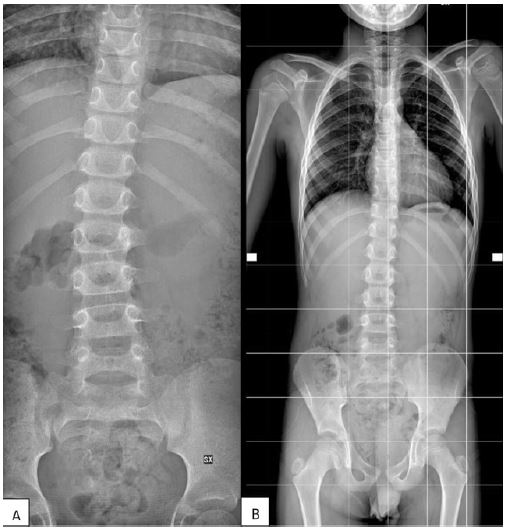

Review of X-Ray of the spine showed a convex right large radius curve (Figure 1). As suspicion was made on bone tumor, MRI scan of the spine was done which revealed a focal alteration of L2 with partial involvement of the left hemi portion of the soma of the entire vertebral peduncle with high signal in the long aTR frequencies. Furthermore, focal alterations of the muscle tissues adjacent to the L2 soma and to the peduncle were also reported (Figure 2).

In fact, we observed that before the surgery the Cobb angle was 12.8° Cobb and 12 months after, it was 7.8° Cobb.

Figure 1: (A) Preoperative X-ray showing right convex scoliosis. (B) 1-year FU X-ray showing reduction of the scoliosis.